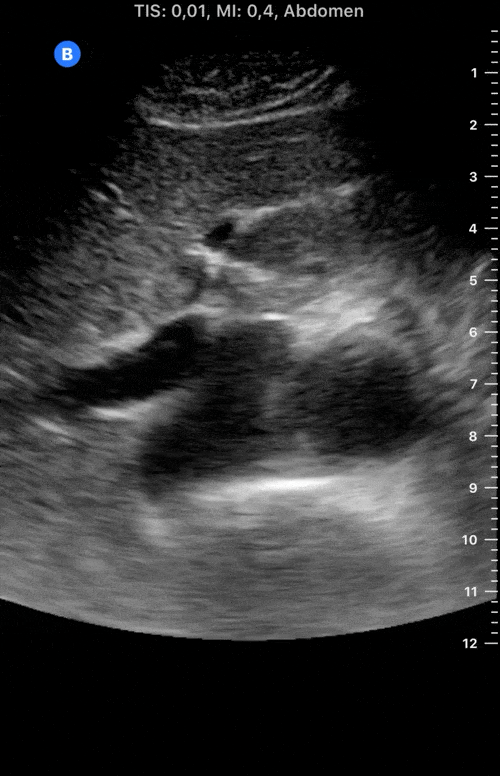

The IVC diameter changes depending on intravascular volume status, and normally, the IVC collapses during spontaneous inspiration. Therefore, the IVC diameter represents a non-invasive method for estimating central venous pressure (CVP). The evidence suggests that in spontaneously breathing patients, there is a good correlation between the sonographic estimation of CVP and values measured with invasive methods (2). IVC filling and CVP, however, allow only a rough correlation with volume status, and the sonographic estimation of preload should at least include the assessment of the LV and the Lung. Thus, it is better to think of IVC filling as an indicator of fluid tolerance, instead of a determinant of fluid responsiveness (6).

IVC exploration is best from the subxiphoid approach with longitudinal and transverse images. The IVC should be assessed in terms of overall size and collapsibility. The diameter is typically measured at its largest (end of expiration) at 1-2 cm distal to where the hepatic veins join the vena cava. An IVC diameter of ≥ 2 cm, especially with minimal or no collapsibility, is considered plethoric and correlates with increased RA pressure. An IVC of < 1 cm, particularly with complete collapse, is considered flat and indicates low preload and potential fluid responsiveness. An IVC diameter between 1 and 2 cm is typically normal.

PITFALLS

In a long-axis view, beware of not sliding off the centre of the vessel, as this will underestimate the size of the IVC and overestimate its collapse. Obtaining long and short axis views may help avoid this pitfall. Another mistake is confusing the descending aorta for the IVC, particularly when scanning in long-axis. Although the IVC may appear to pulsate, the aorta has a thicker wall, and its position is to the patient’s left. Following the IVC upwards will reveal the hepatic veins junction and the entrance to the RA, while the aorta will travel behind the heart. The IVC moves both anterolaterally and craniocaudally with inspiration, and this should be considered during visualization or measuring. For this very reason, measuring in M-mode is not recommended as it would not be accurate.

SHOCK

In a shocked patient, a flat or highly collapsible IVC correlates well with low preload estates (hypovolaemia, haemorrhage, sepsis). Yet by itself, a small IVC is not enough to define low preload and could also represent a normal finding.

Conversely, a distended, not collapsing IVC suggests distal obstruction in a shocked patient. Potential causes include LV failure, massive PE, tension pneumothorax and cardiac tamponade. Nonetheless, there are other causes of elevated cava / RA pressure, such as chronic pulmonary hypertension.